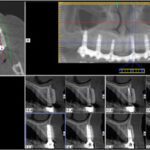

Επίσης, πλέον μία πολύ συχνή επέμβαση είναι η τοποθέτηση οστικού μοσχεύματος στα ιγμόρια άντρα για δημιουργία οστικού όγκου, με σκοπό την τοποθέτηση οδοντικών εμφυτευμάτων στην άνω γνάθο.

Αποτελεί και αυτή επέμβαση ρουτίνας για τους Στοματικούς και Γναθοπροσωπικούς Χειριουργούς, με αποτέλεσμα που αγγίζει σχεδόν πάντα το άριστο. Και εδώ το πιό συχνό αίτιο αποτυχίας, είναι το ίδιο όπως αναφέρθηκε πρωτύτερα για τους φρονιμίτες. Είναι πλέον γνωστό σε όλους ότι τα οδοντικά εμφυτεύματα συμβάλλουν στην αποκατάσταση της λειτουργίας της μάσησης, της κατάλληλης σύγκλισης και της διατήρησης  του οδοντικού φραγμο